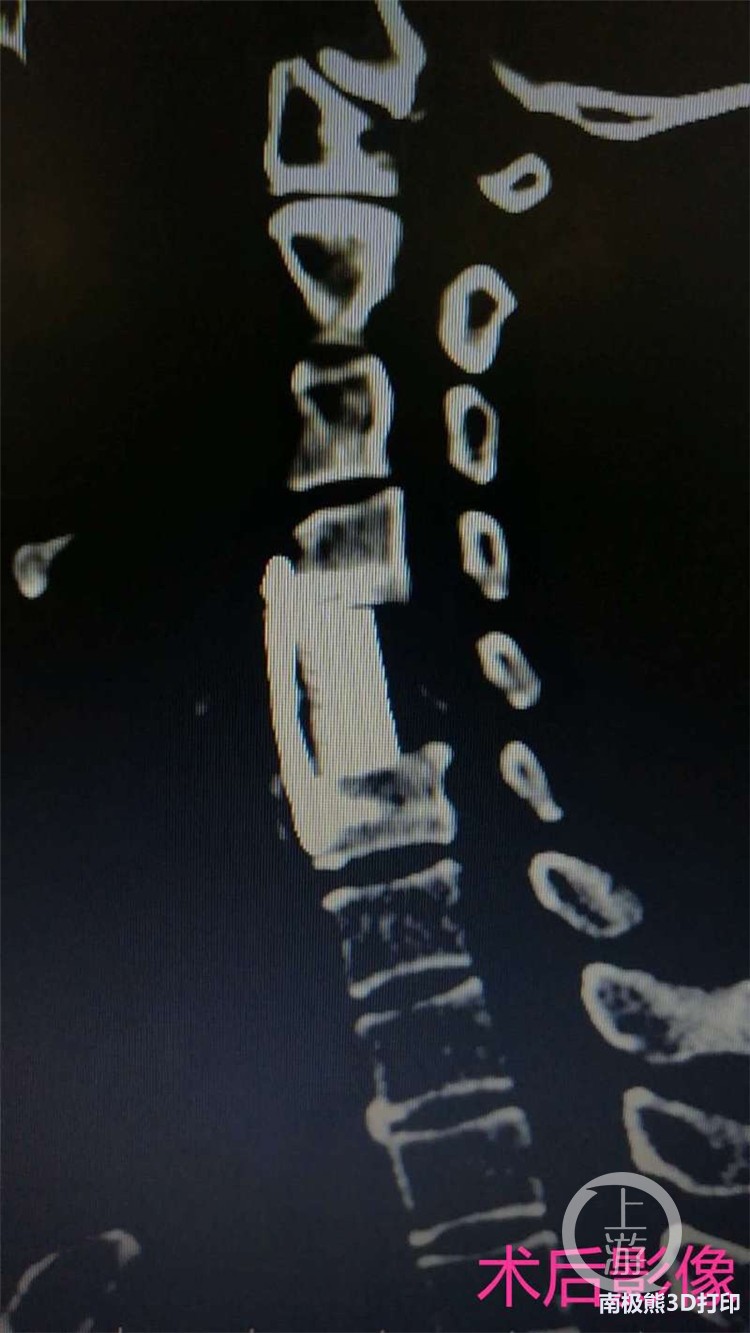

术前,该科依据患者最新的CT和MRI的影像学数据资料,通过医工结合和反复论证,按照1:1的3D打印复制模型,制造出一个长度2厘米、直径1.4厘米大小的立体精确全颈椎假体。术中,在麻醉科配合下,刘鹏主任团队在显微镜辅助下实施手术,成功完成3D打印人工颈椎椎体植入手术。术后次日,患者即可下地,症状完全消失。 据刘鹏主任介绍,3D打印是骨科领域近年来快速发展的领域之一,该院骨科中心一直注重探索和尝试骨科智能化诊疗手段,为广大患者解除病痛谋福。该人工椎体是由钛合金粉末通过3D打印技术制造完成,具有良好的生物相容性。同时,3D打印的骨小梁结构,拥有类松质骨的弹性模量,避免了应力遮挡和骨吸收,还可以诱导骨细胞进行迁移和增殖,具有可靠的骨整合性。椎体与上下相邻节段终板之间是面与面的接触,可以有效地避免椎体终板塌陷和椎间高度丢失等问题,医学前景及临床意义极大。